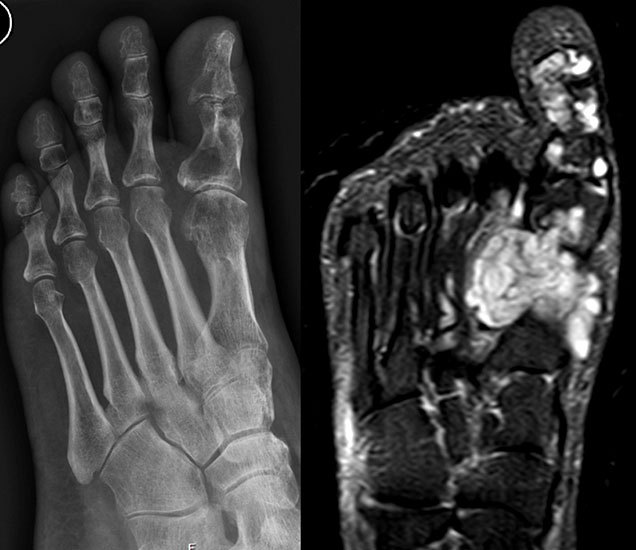

Enchondrom

Das Enchondrom ist der häufigste Knochentumor im Bereich von Hand und Fuß und nach dem Osteochondrom der zweithäufigste gutartige Knochentumor überhaupt. Die geschlechtliche Verteilung ist ausgeglichen, Enchondrome finden sich meist bei Patienten zwischen 20-40 Jahren. Dieser chondrogene Tumor verhält sich meist asymptomatisch, kann aber durch eine Knochenexpansion und Schwellung sowie Spontanfrakturen (Abb. 17) auffallen. Radiologisch zeigen sich in der Regel gut abgrenzbare Osteolysen, Matrixverkalkungen sind typisch aber nicht obligat. Die MRT zeigt typischerweise eine annähernd flüssigkeitsäquivalente Signal­qualität mit niedrigen Signalintensitäten in T1 und hoher Signalgebung in T2, die Binnen­struktur weist eine für chondrogene Tumoren typische Lobulierung mit KM-Aufnahme auf.

Im Gegensatz zu Osteochondromen ist die Lage von Enchondromen nicht auf die Metaphyse beschränkt. Sie finden sich auch im Bereich der Epi- und Diaphysen. Die kurzen tubulären Knochen der Metatarsalia und Phalangen sind bevorzugt betroffen. Hier findet sich die Läsion typischerweise im Bereich der proximalen Phalangen oder distalen Metatarsalia, eine Ausbreitung auf die gesamte Diaphyse ist von hier aus jedoch nicht ungewöhnlich. Die Möglichkeit einer malignen Entartung (Chondrosarkom) ist im Bereich der Metatarsalia und Phalangen im Vergleich zu den langen Röhrenknochen und platten Knochen extrem selten 33. Die übliche Therapie besteht in einer gründlichen Curettage. Je nach Größe des Defekts und Schwächung der Kortikalis kann die Transplantation eines stabilisierenden kortiko­spongiösen Spans notwendig werden. Zusätzliche osteosynthetische Verfahren sind nur selten erforderlich.